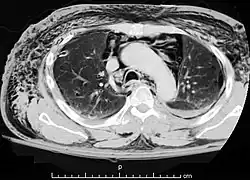

![]() КТ-изображение: эмфизема средостения у больного со спонтанным пневмомедиастинумом | |

Компьютерная томография органов грудной клетки

Компьютерная томография является наиболее эффективным методом диагностики эмфиземы средостения, так как с его помощью легко выявляется наличие газа в средостении, на поперечных сечениях хорошо определяется его локализация и распространённость эмфиземы. Преимуществом перед рентгенографией является возможность диагностики пневмомедиастинума даже в тех случаях, когда имеется выраженная эмфизема мягких тканей грудной стенки, сводящая информативность рентгенографии в этой ситуации к минимуму. Кроме того, компьютерная томография позволяет провести дифференциальную диагностику спонтанного пневмомедиастинума и других заболеваний с похожей клинической картиной, а также важна для установления причины заболевания[2][21].